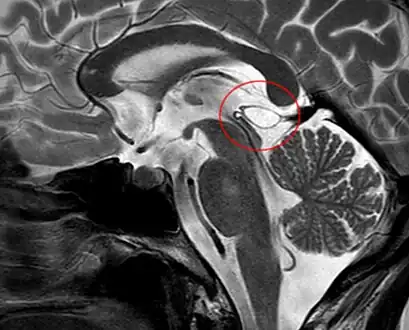

Another case: sagittal